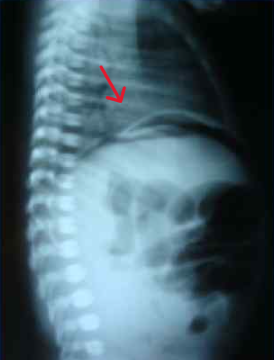

At 37 hours of life, with a diagnosis of intestinal obstruction, perforation of a hollow organ, he was transferred for surgical care to the neonatal intensive care unit of the regional children's clinical hospital in severe condition on mechanical ventilation. Abdominal X-rays revealed the "sickle" sign characteristic of pneumoperitoneum (Fig. 4).

Fig. 4: Abdominal X-ray showing the characteristic "sickle" sign of pneumoperitoneum